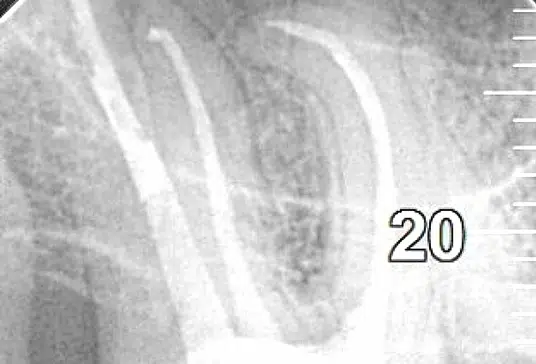

Na pierwszej wizycie przeprowadzamy wywiad medyczny z pacjentem oraz dokładne badanie stanu jamy ustnej. Wykonujemy badania radiologiczne, takie jak Pantomogram i zdjęcia RTG zęba, którego ból zgłasza pacjent. Na podstawie tych zdjęć diagnozujemy stan zęba i kwalifikujemy go do leczenia endodontycznego.

Po zakończonym leczeniu endodontycznym zalecamy pacjentom wizyty kontrolne co 6 miesięcy. Podczas tych wizyt wykonujemy zdjęcie punktowe RVG, które pozwala ocenić stan tkanek okołowierzchołkowych i skuteczność przeprowadzonego leczenia kanałowego.